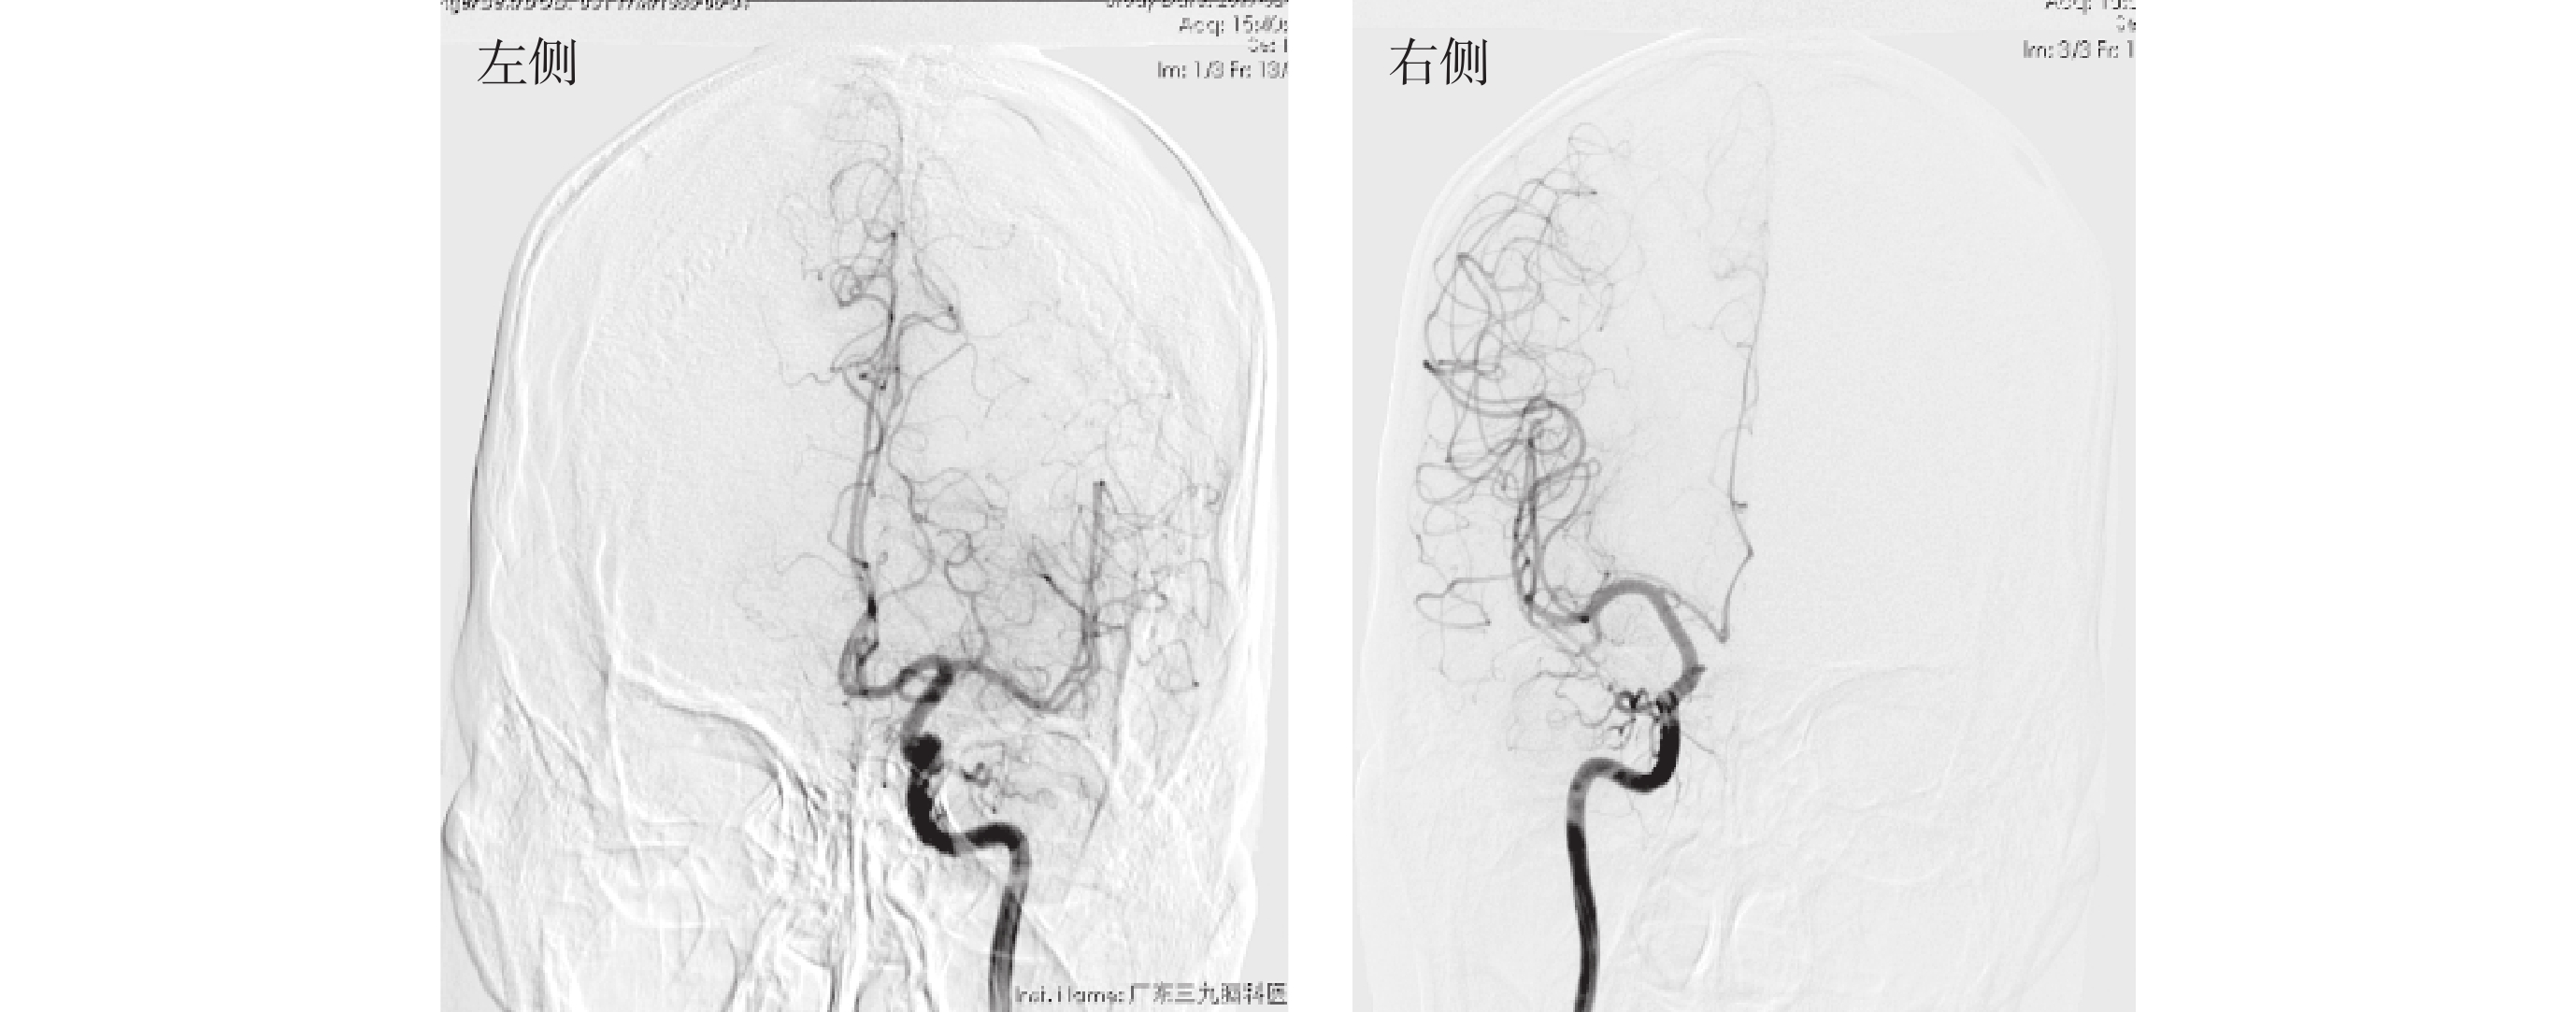

1.2.3 Wada實驗

在本次研究中,Wada實驗由癲癇中心的神經外科醫生負責操作。在Wada實驗過程中,臨床醫生通過分別向雙側頸內動脈一定量異丙酚(根據患者的耐受性以及患者的年齡確定)有選擇的阻斷一側大腦功能,同時患者需要完成圖片命名任務。導致患者無法配合完成Wada實驗或者對患者的生命健康造成嚴重威脅時,停止后續操作并由臨床醫生進行緊急處理。

在左側頸內動脈注射8 mg異丙酚時患者出現語言抑制。在右側頸內動脈注射6 mg異丙酚時,患者出現語言抑制。根據Wada的結果,該例患者的語言優勢半球為雙側